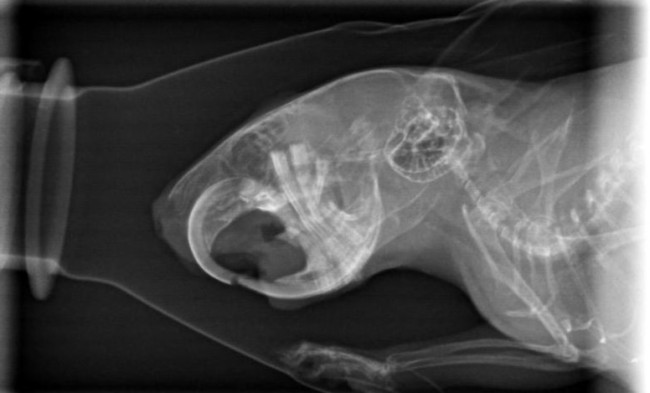

heute gab es doch ein Kontrollröntgen.

Gerade weil es vor Weihnachten super stressig ist, hab ich gesagt sie sollens nur machen, wenns zeitlich rein passt. Und hat es wohl

Hier könnt ihr mit gucken:

Der Unterschied zwischen diesen und den ersten Bildern beträgt übrigens 2 Monate (und ein Tag)

Wow, ohne davon wirklich Ahnung zu haben, sieht man auf den beiden Fotos von oben geröntgt sehr deutlich die positive Entwicklung

Nun ist es so, dass ihr Kiefer nicht komplett grade zusammengewachsen ist. Das war mir schon fast klar, da wurde ja nix fixiert.

Somit sind wir nun in aktuell noch sehr kurzen Abständen Gäste beim Zähnemachen.